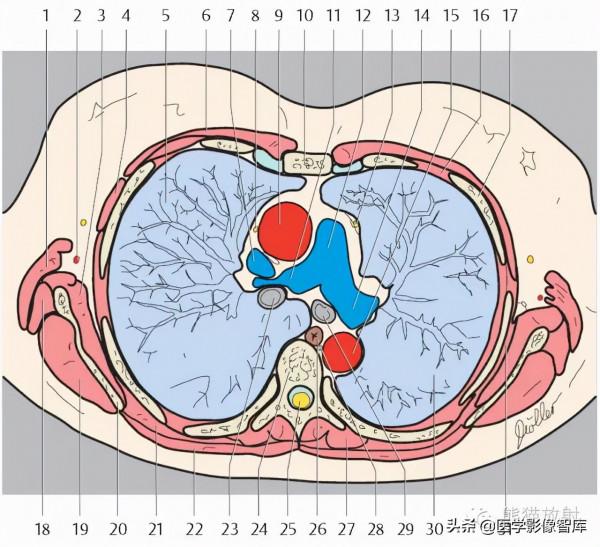

第八層:肺動脈幹水平

1. Latissimus dorsi muscle 背闊肌

2. Long thoracic nerve 胸長神經

3. Serratus anterior muscle 前鋸肌

4. Glandular tissue of the breast and nipple 乳腺腺體及乳頭

5. Right lung 右肺

6. Pectoralis major muscle 胸大肌

7. Right pulmonary artery 右肺動脈

8. Superior vena cava 上腔靜脈

9. Internal thoracic artery and vein 胸內動脈、靜脈

10. Ascending aorta 升主動脈

11. Sternum 胸骨

12. Pulmonary trunk 肺動脈幹

13. Rib (costal cartilage) 肋骨(肋軟骨)

14. Left pulmonary vein 左肺靜脈

15. Left atrium 左心房

16. Intercostal muscle 肋間肌

17. Rib 肋骨

18. Teres major muscle 大圓肌

19. Infraspinatus muscle 岡下肌

20. Scapula 肩胛骨

21. Trapezius muscle 斜方肌

22. Right inferior lobar bronchus 右肺下葉支氣管

23. Erector spinae muscle 豎脊肌

24. Thoracic vertebra 胸椎

25. Spinal cord 脊髓

26. Azygos vein 奇靜脈

27. Thoracic duct 胸導管

28. Esophagus 食管

29. Descending aorta 降主動脈

30. Left inferior lobar bronchus 左肺下葉支氣管

31. Rhomboid muscle major 菱形肌

32. Left lung 左肺

33. Subscapularis muscle 肩胛下肌